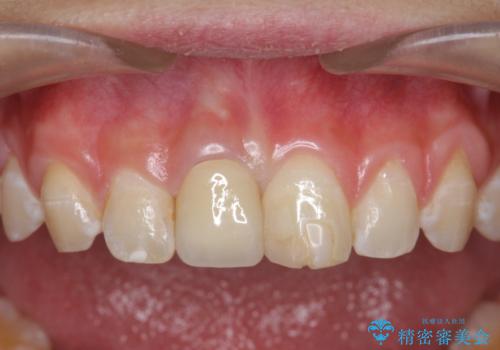

前歯をきれいにしたい ジルコニアクラウンによる審美治療

- 前歯の見た目の改善を求めて来院されました。

ジルコニアクラウンによる審美性の改善を計画します。

失活歯のため捻転を改善し、根管治療は特に希望されなかったのでそのままとしました。

今回失活歯であったため捻転を取り反対側の前歯に揃えて補綴を行うことができました。